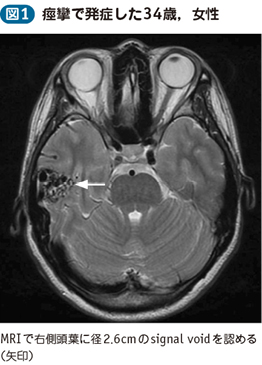

Neurosurgery10 脳動静脈奇形治療のこれまでとこれから 新到着 新NS 10】脳動静脈奇形治療のこれまでとこれから NOWの詳細情報

新到着 新NS 10】脳動静脈奇形治療のこれまでとこれから NOW。脳神経外科 専門治療 脳動静脈奇形|東京慈恵会医科大学附属柏病院。脳・脊髄動静脈奇形と頭蓋内・脊髄硬膜動静脈瘻。2017年発行の第1版です。【JMECC受講テキスト】内科救急診療指針2022【裁断済み】。脳神経領域:320列面検出器CTの最新画像がもたらす新たな展開。よろしくお願い致します。